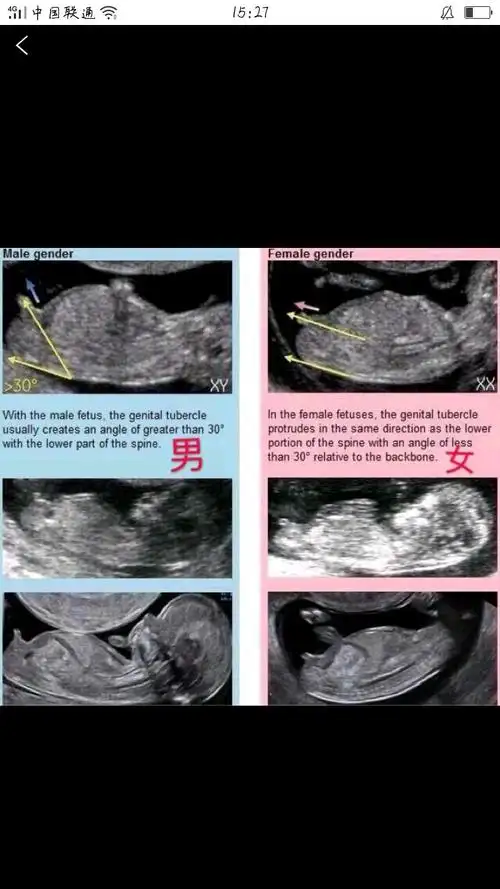

nt图上的nub点看生男生女的准确率高吗

nt测值看男女准确率高达80这2个数据你看对了吗

12周做的nt,上面的亮点是什么,能看出男女么